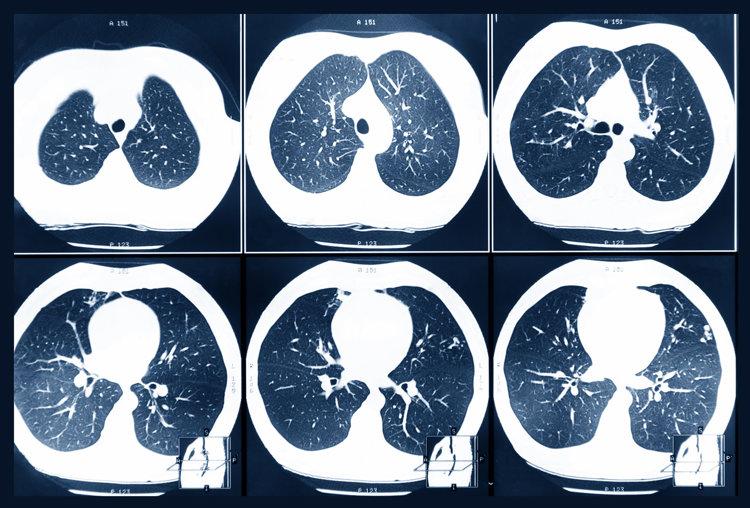

3、低劑量螺旋CT

低劑量螺旋CT檢查是篩查肺癌的首選方案,具有簡便、易行、高靈敏度等特點,其敏感性是普通胸片的4~6倍,可及時發現微小結節以及腫瘤的形態和位置。

2、實性結節、部分實性結節、磨玻璃結節

三種結節中實性結節的安全性最高,磨玻璃結節次之,部分實性結節相對危險一些。尤其是結節邊緣不規則、生長速度快、帶毛刺等特點,要高度警惕是惡性的。